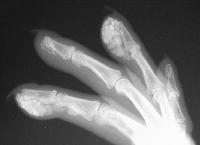

Xrays show extensive soft tissue calcifications of the distal pulp of these fingers.

Soft tissue calcifications are typically diffuse, and can not be simply "shelled out". Thorough excision may lead to extensive skin loss, and partial removal (limited incision and drainage) may be a reasonable compromise approach in selected cases.

Healing ulcerations on the left index and middle fingertips, where calcium deposits have spontaneously drained in the past.